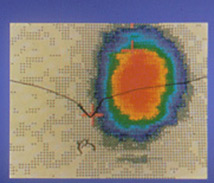

La scintigraphie thyroïdienne au technétium

Scintigraphie. Nodule toxique (extinctif)